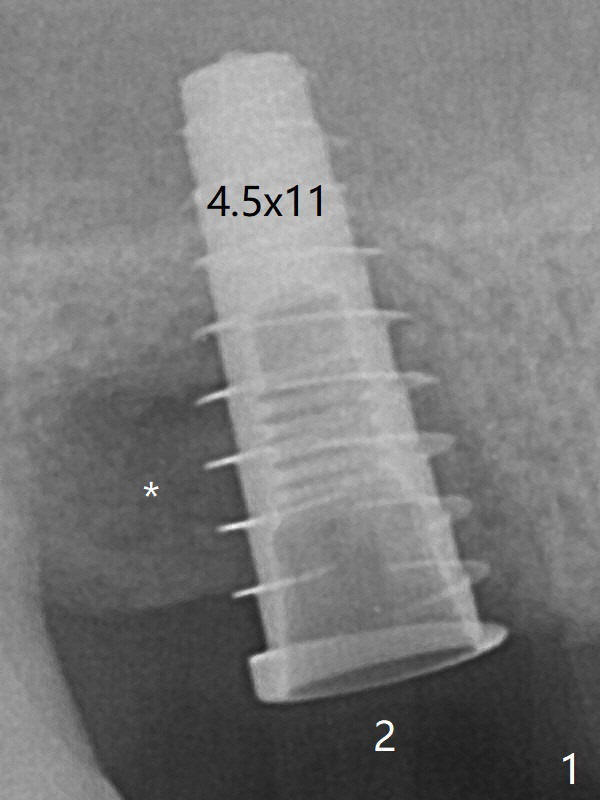

The tooth #2 has severe distobucal (DB) infection before and after extraction (Fig.1 *); sinus lift is done with 4.5x11 mm dummy implant using guide